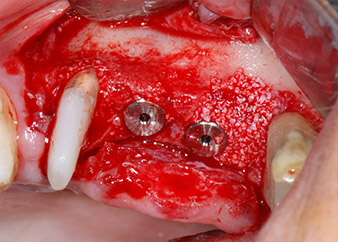

Vor der Insertion der Implantate und nach Überprüfung der intakten Schneiderschen Membran (Abb.9) wurde der interne Sinusboden an beiden Implantatpositionen mittels eines xenogenen Knochenersatzmaterials (Abb. 10) augmentiert.

Dann wurden die Implantate (Restore, Keystone Dental) mit dem Implantatmotor eingesetzt (Abb. 11 und 12).